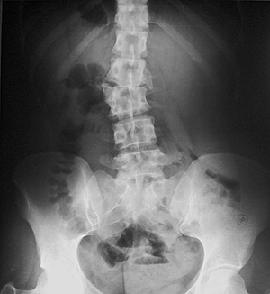

Диагностика остеохондроза подразумевает использование различных методов, прежде всего, пальпацию поясничного отдела. Для подтверждения диагноза больной направляется на обследование с помощью диагностической аппаратуры.

- Рентгенография помогает оценить состояние позвоночного столба и каждого позвонка по отдельности. Опосредовано судят и о целостности межпозвоночных дисков и спинномозгового канала.